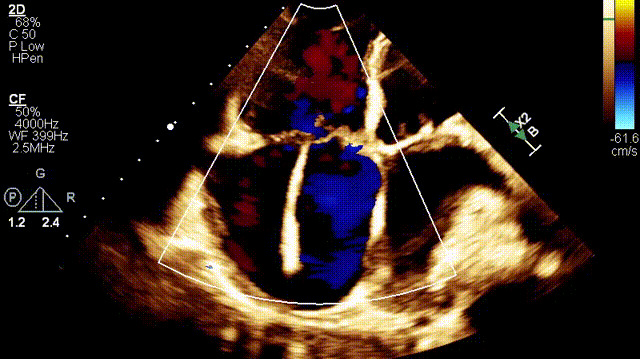

植入前超聲

手術(shù)在全麻狀態(tài)下開(kāi)展,此次手術(shù)采用經(jīng)右側(cè)頸靜脈入路的方式將輸送器送入患者心臟內(nèi),在TEE及DSA引導(dǎo)下調(diào)整輸送器頭端角度,使得輸送器與三尖瓣瓣環(huán)平面垂直。在輸送器進(jìn)入右心室后釋放室間隔錨定裝置,而后釋放瓣葉夾持件(2個(gè)耳片結(jié)構(gòu))成垂直狀態(tài)。在TEE及DSA確定夾持件固定至三尖瓣葉根部且位于右室側(cè)后釋放人工瓣心房側(cè)盤(pán)片。隨后調(diào)整瓣膜同軸性以及室間隔錨定件位置(貼合室間隔),前推藏針管并固定,進(jìn)而釋放室間隔錨定裝置,并再次確認(rèn)瓣膜位置、穩(wěn)定性及同軸性,合攏輸送鞘后撤出輸送器,完成LuX-Valve Plus人工三尖瓣瓣膜的植入。